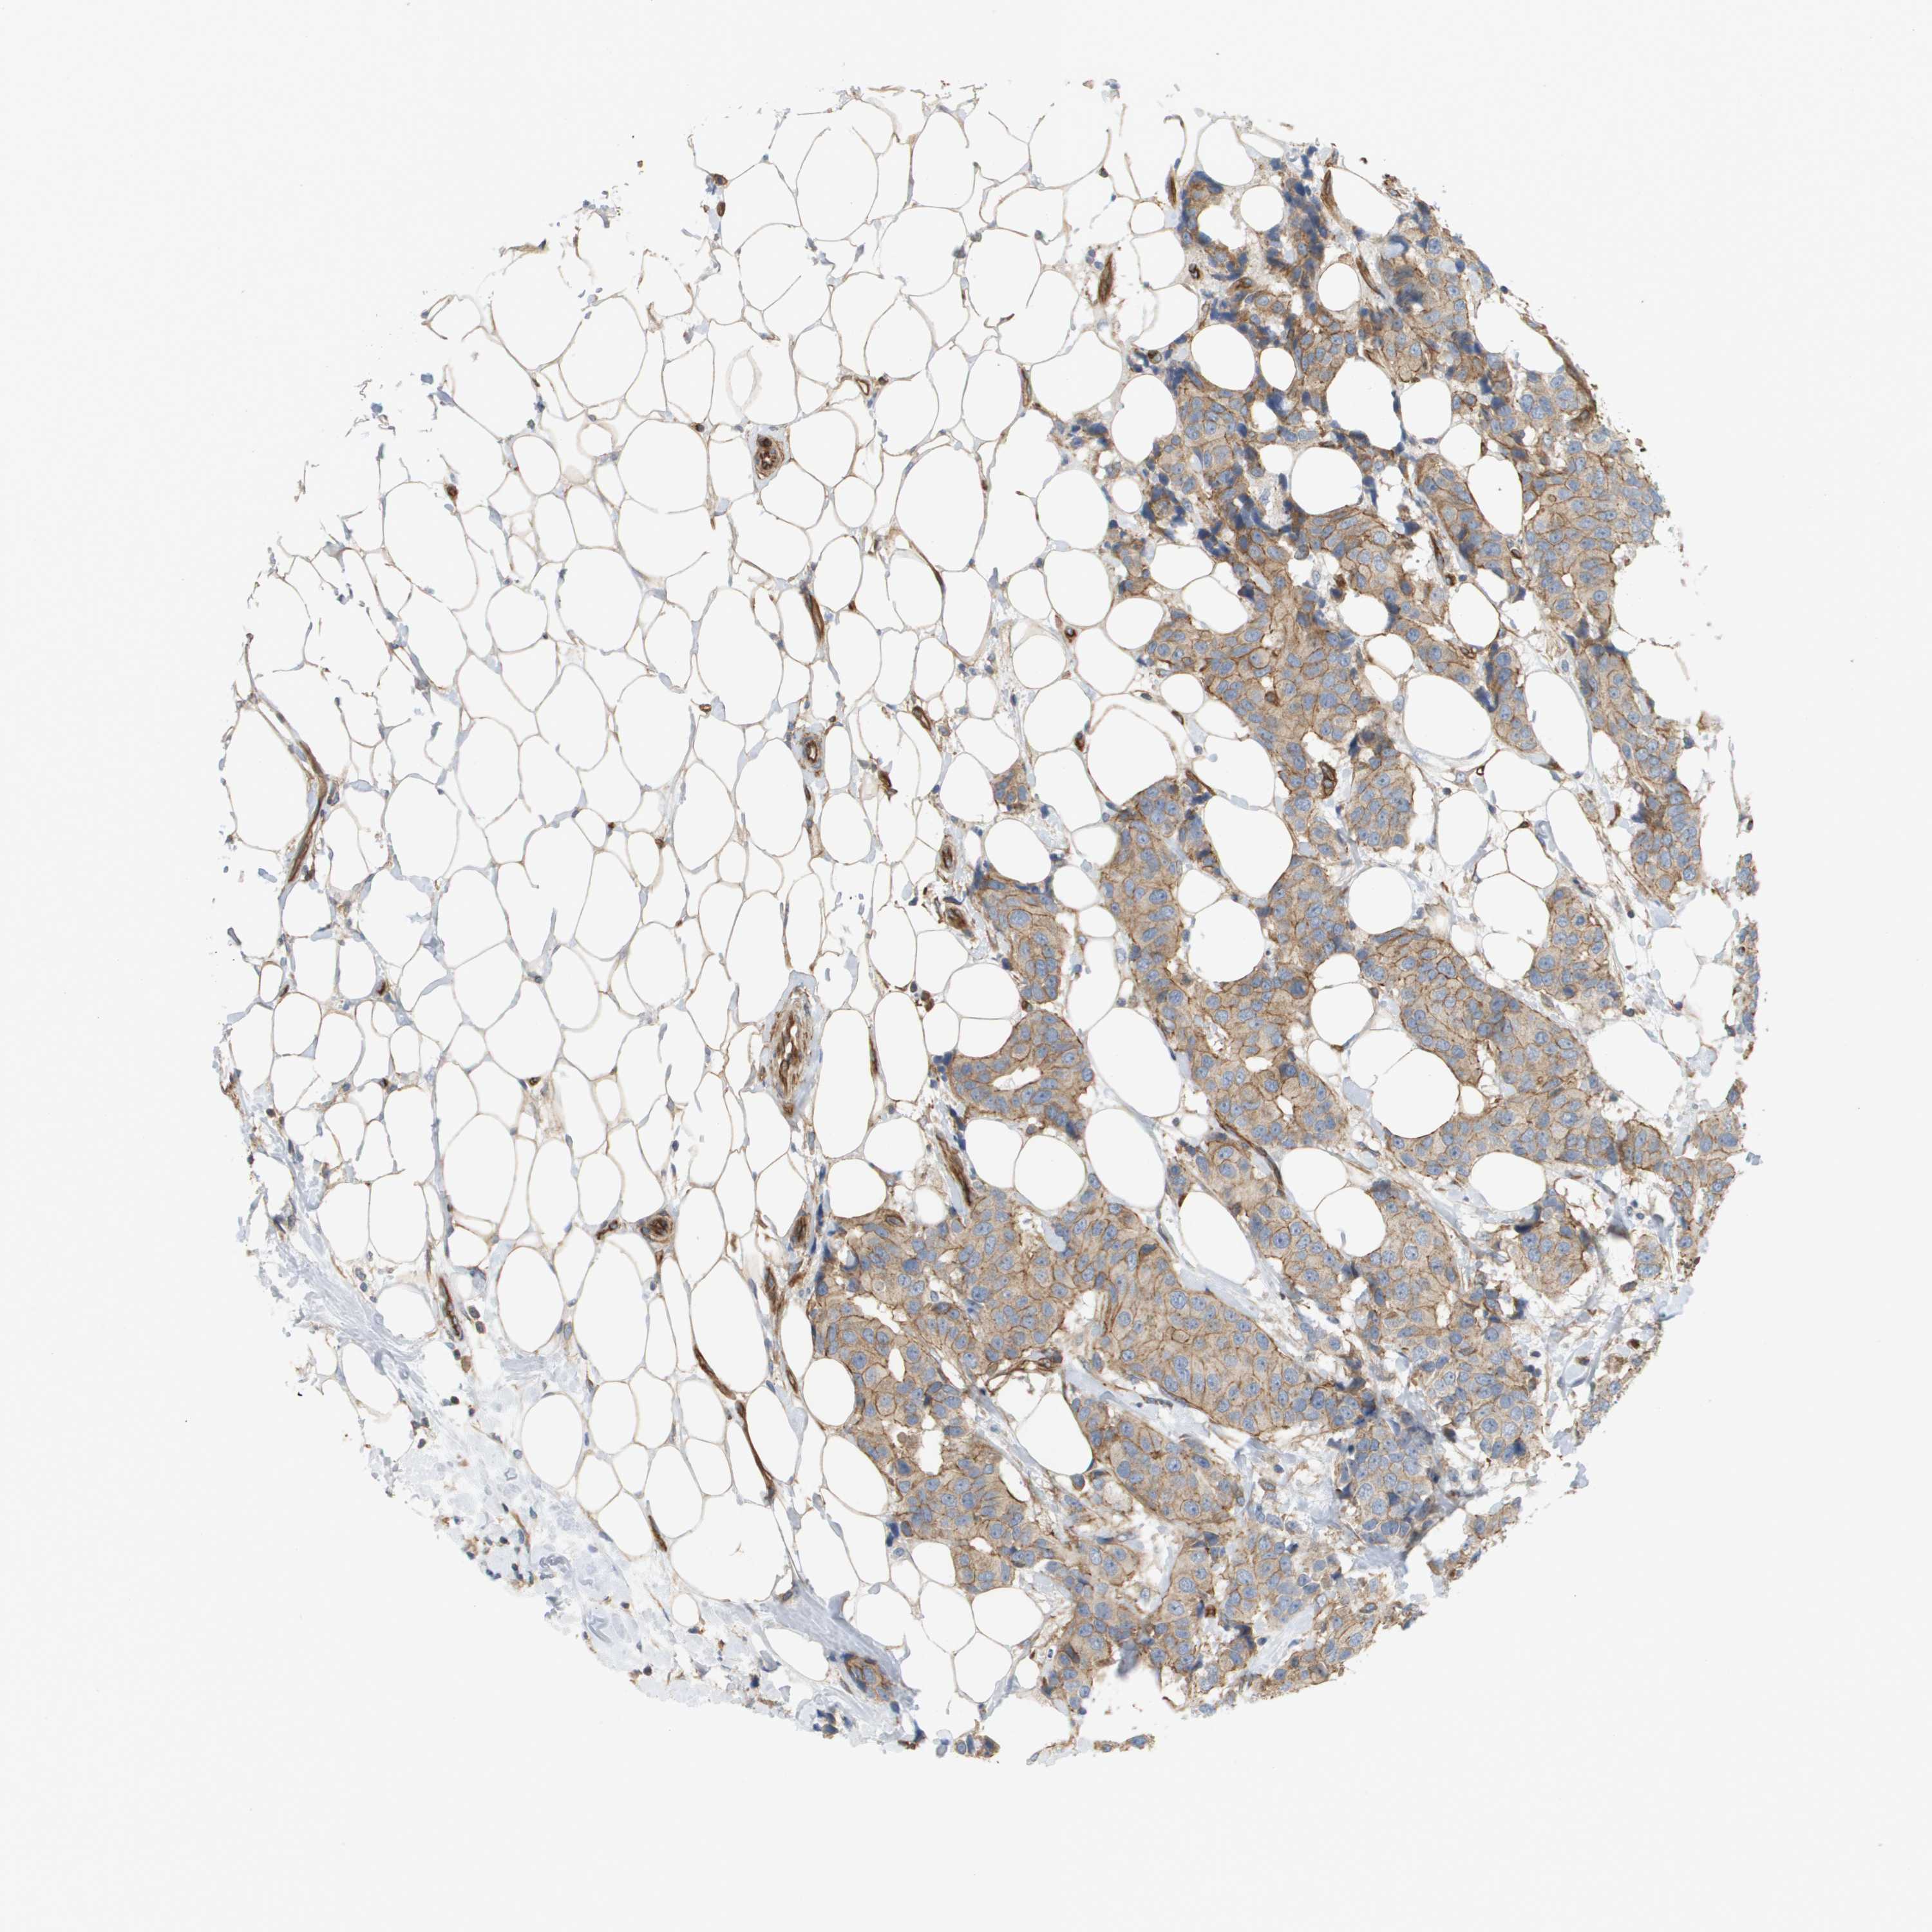

CANCER BREAST CANCER Show tissue menu

BRCA TCGA BRCA VALIDATION PROTEIN EXPRESSION